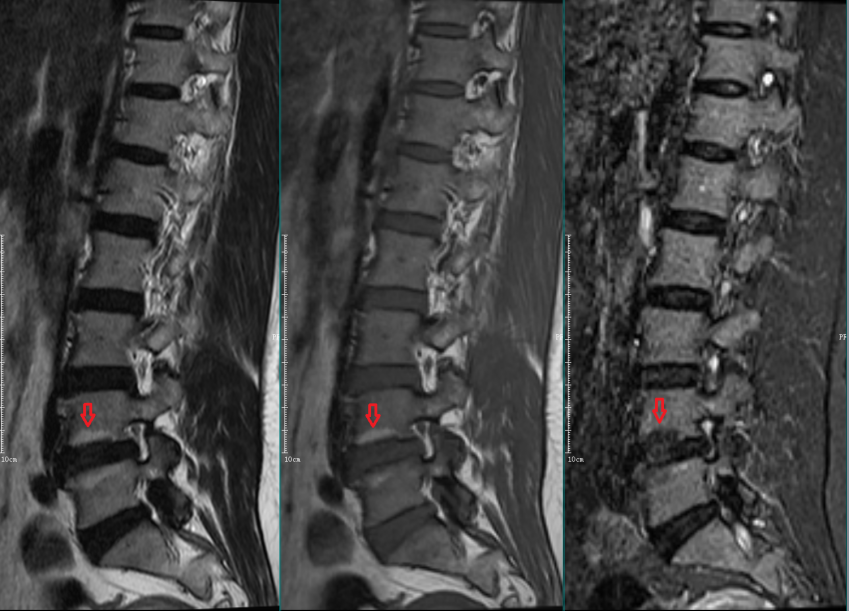

Modic Ⅰ型:

L4-5椎间盘上下缘见条带状异常信号,T1WI低信号,T2WI高信号,STIR序列高信号。

L5-S1椎间盘上下缘见条带状异常信号,T1WI低信号,T2WI高信号,STIR序列高信号。